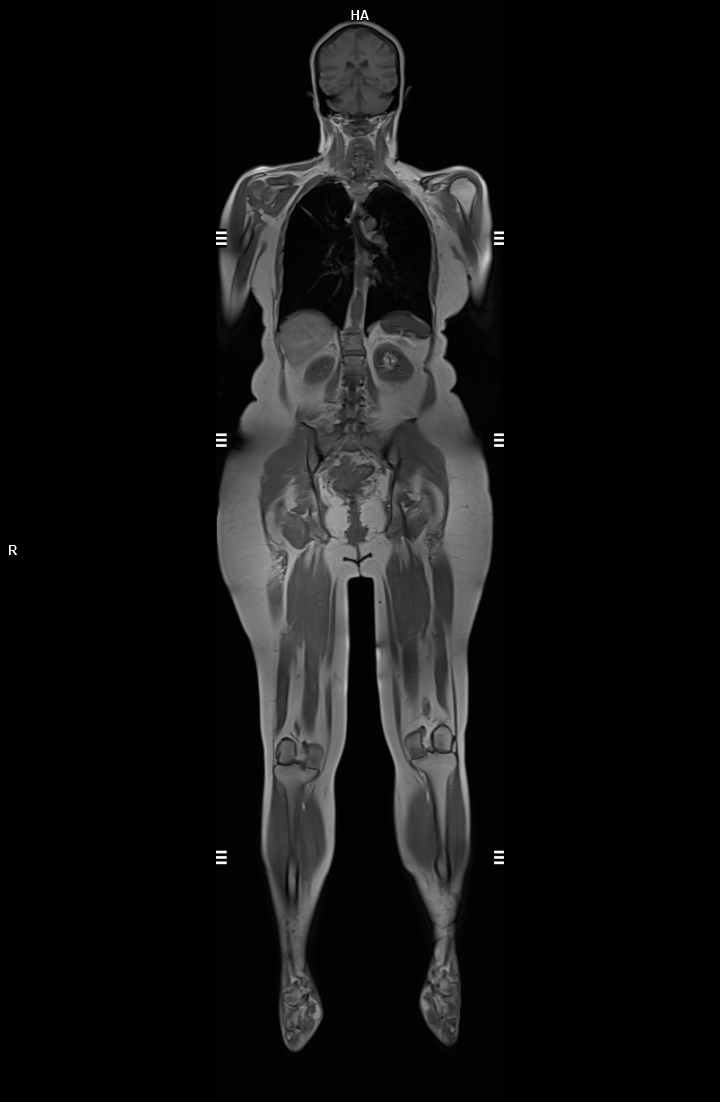

• Tüm Vücut MR

• 3 TESLA MR ÇEKİM GÖRÜNTÜLERİ

3 Tesla MR Çekim Görüntüleri

• 3 Tesla MR Çekim Görüntüleri